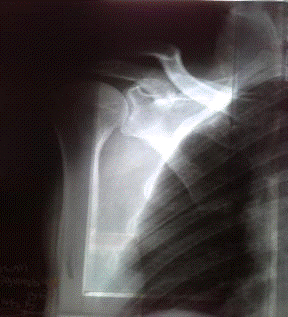

Диагностика перелома ключицы: различия и симптомы